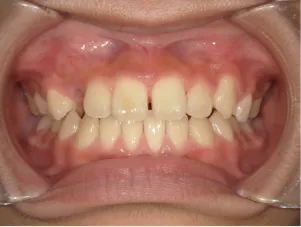

治療前①小5:スタート

| はじめのご相談 | 凸凹になりそうと一般歯科の先生に言われたのでみてほしい |

|---|---|

| カウンセリング・診断結果 | 下あごが後退しているタイプの出っ歯で、過蓋咬合で下あごが前に成長しにくいタイプの顔立ちです。 上の歯列弓が小さめで前歯に凸凹があります。 口元が閉じにくい口唇閉鎖不全があります。 *上記に対する治療の流れを説明し(拡大・前歯の並べ替え→出っ歯の改善→モノブロック装置(筋機能的咬合誘導装置)→必要によりマルチブラケット法)、以下の治療を提案しました。 |

| 行ったご提案・診断内容 | 成長期に行う治療と咬合治療をご提案しました。 成長期治療(成長時期にお口の環境を整え、適正な成長を促す治療)で、 ①歯列弓形態の修正、拡大と前歯を並べる。 ②出っ歯を治す専用の装置を使用する。 ③・MFT:舌や口唇などが正しい動きやポジショニングで機能し、鼻で呼吸できるようにする練習、毎日おうちで習慣づくように続けてもらいます。 ④拡大による顎顔面の適正な成長効果で口元を改善する(写真③)。 |

| 治療期間 | 小5~中3 |

| おおよその費用 | 1,089,000円 |